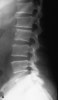

- X-ray : 최초의 방사선학적 소견은 인접한 종판(end plate)의 희박화(rarefaction)이며, 감염된 후 최소 2주에서 3개월은 지나야 발견 가능합니다.

X-ray : 척추 감염(Spinal infection)